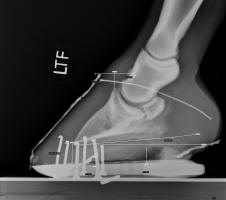

[Fig 1- 4 pictures below] Before taking radiographs, the investigators used the CS measurements to predict 3 degree palmar angle and a 16mm sole depth

The radiograph below verified that the predictions were reasonably accurate. The accuracy of these predictions is made possible by the consistency of the externally visible collateral sulci to the third phalanx [red arrow below]